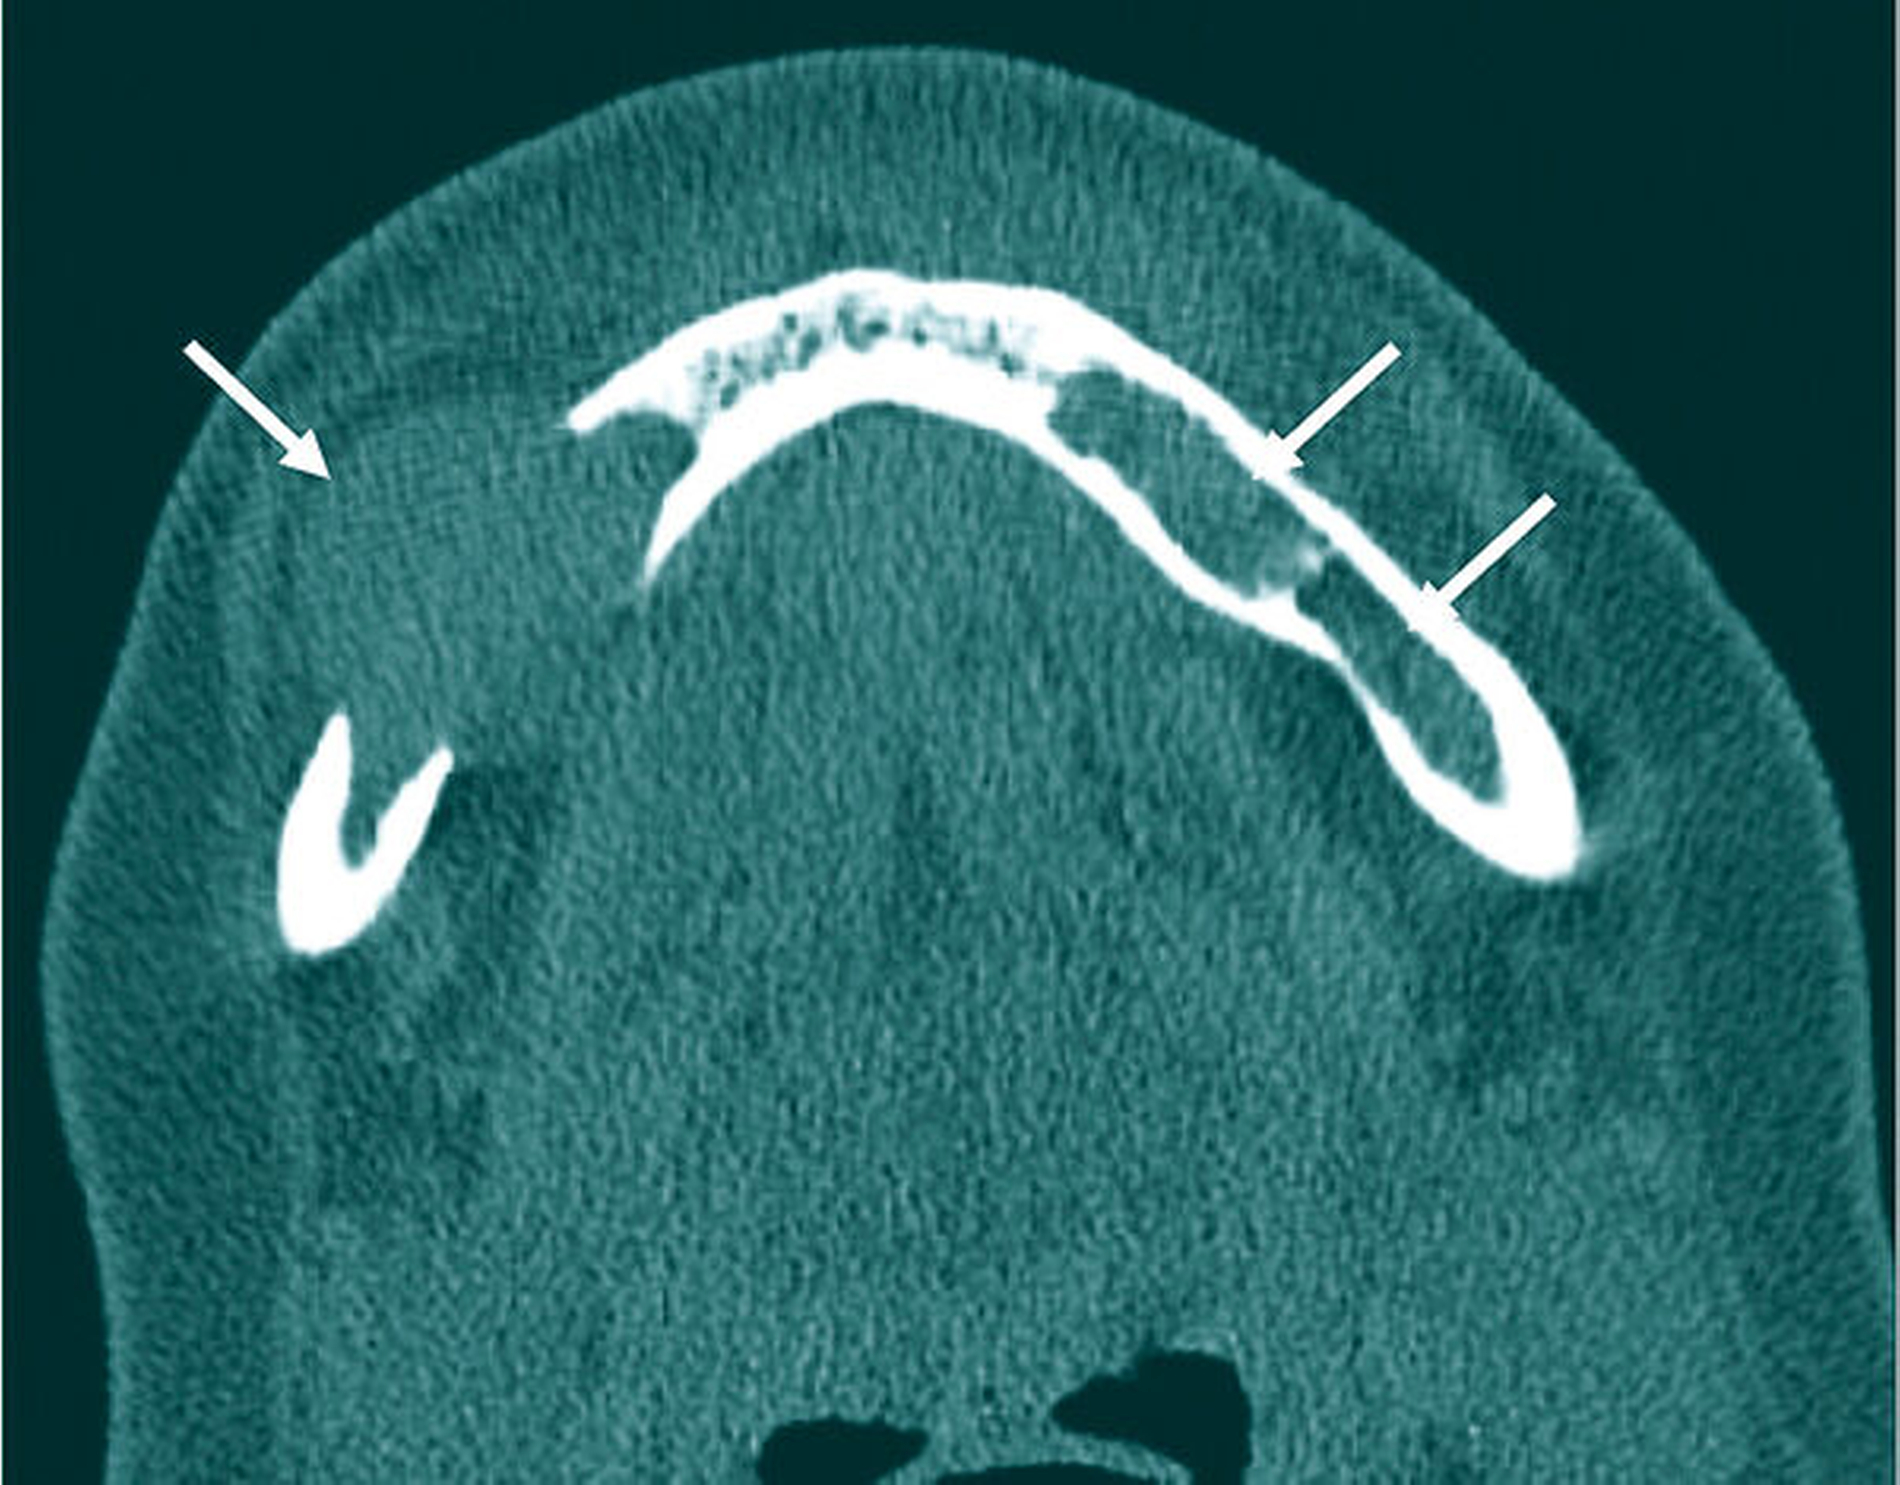

Das Orthopantomogramm zeigte eine auffällige, homogene, scharf begrenzte osteolytische Veränderung in regio 43 bis 46 ohne Resorption der angrenzenden Zahnwurzeln, allerdings mit Destruktion der Corpusunterkante korrespondierend zur klinisch evidenten Auftreibung des Unterkiefers. Daneben waren weitere osteolytische Läsionen zu verzeichnen, die sich subtotal über die gesamte Mandibula verteilten (Abbildung 1). Die Computertomografie des Unterkiefers bestätigte das Vorliegen multipler disseminierter osteolytischer Prozesse (Abbildung 4).

Anhand spezifischer Laboruntersuchungen wie Eiweißelektrophorese und Immunfixation einschließlich Knochenmarkspunktion konnte die Diagnose Multiples Myelom gesichert werden. Die Ganzkörper-Low-Dose-CT ergab einen multifokalen Befall weiterer Teile des Skeletts (Abbildung 5) mit Kompressionsfraktur des dritten Halswirbelkörpers. Eine gezielte kombinierte Therapie mit Bortezomib, Lenalidomid, Dexamthason sowie Denosumab wurde in kurativer Intention binnen einer Woche eingeleitet. Zahnärztlich-chirurgischer Sanierungsbedarf ergab sich bezüglich der Einleitung der antiresorptiven Therapie nicht. Eine konservierende sowie eine Parodontaltherapie über den Hauszahnarzt wurden empfohlen.